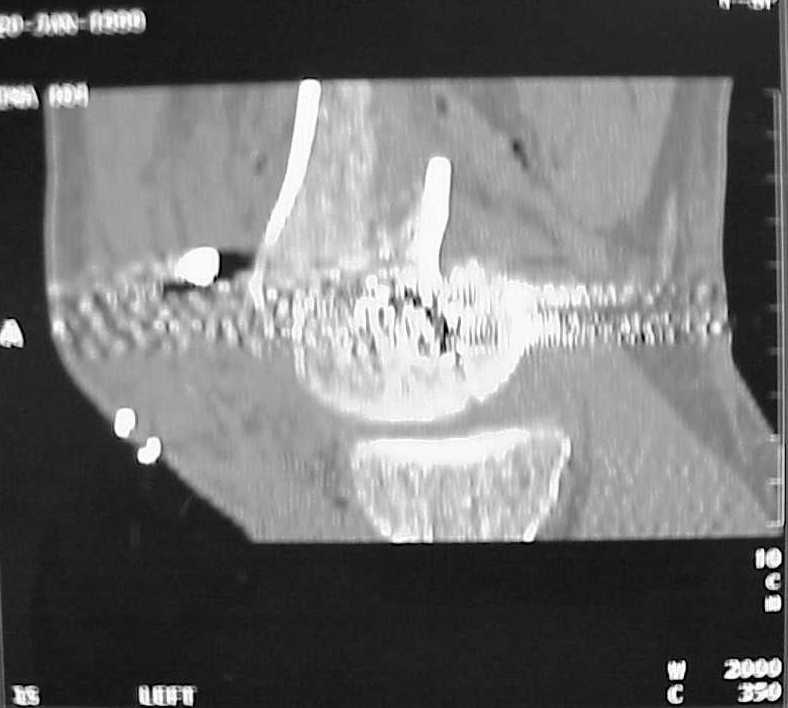

So I think a TAC of the knee could be useful.

I am sure that you assessed adequately the condylar fractures, they may need fixation (eg. percutaneous screws).

A CT and knee xrays would help identify lateral condyle comminution and/or a "hoffa fragment" of the posterior condyle. I am concerned that the lateral cortex is not sufficient to give purchase for a retrograde IMN. blocking screws could improve this as a possibility. A long blade or LISS if avaible would be my secondary choices. Good luck. Any chance you can get these cases transferred earlier when it

Мы пошли на операцию с планом попытаться сделать закрытый интрамедулярный, а не получится - сделать аппаратом. Посчитали, что получилось, хотя на еженедельной конференции ожидаются некоторые проблемы с объяснениями ;-)

Насчет стабильности для ранней нагрузки, конечно, сомнительно, но при таком повреждении ранняя нагрузка противопоказана в любом случае. Для ранних движений Должно хватить. Снимки в следующем сообщении.